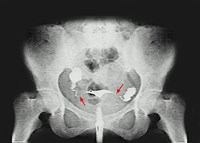

Наиболее частой причиной женского бесплодия (в 70% случаев) являются воспалительные заболевания маточных труб и яичников, вызванные возбудителями, передаваемыми половым путем, или осложнениями аборта. При этом возникает непроходимость маточных труб. Наиболее частые причины мужского бесплодия: